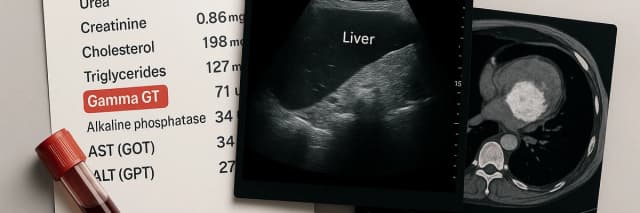

Gamma GT élevé : analyses, imagerie et suivi médical. Découvrez les examens indispensables pour identifier la cause et agir sur votre santé.